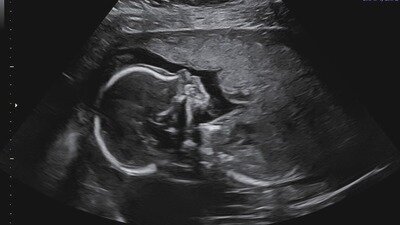

I am Athena, a mother who came dangerously close to losing her life during childbirth. Preeclampsia, PPROM, and postpartum hemorrhage complicated my pregnancy and delivery. Conditions that escalated so quickly, they left me fighting for survival. My son was born prematurely at just 32 weeks, his tiny body forced into the world far sooner than it should have been. In those moments, nothing was guaranteed. Not his first breath, not my recovery, not our future together.